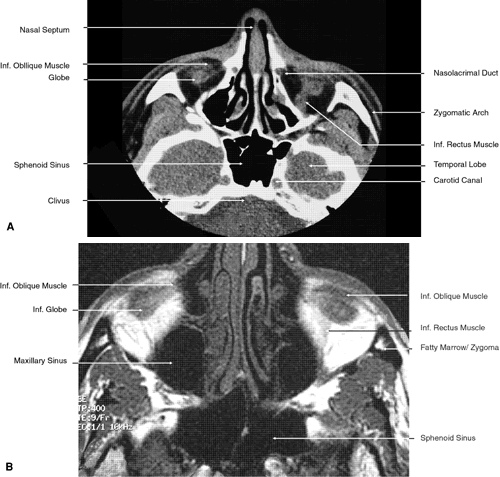

The globe is shown in Figure 12. The orbit and periorbital structures are shown in Figures 13 through 16, and the optic canal is shown in Figures 17 through 26. The cavernous sinus and optic chiasm are shown in Figures 27 and 28, and the posterior visual pathway and cranial nerves are shown in Figures 29 through 33.

Fig. 22. Axial images at the level of inferior orbit. A. Computed tomography scan. B. T1-weighted magnetic resonance imaging.

Fig. 23. Axial images at the level of midorbit. A. Computed tomography scan. B. T1-weighted magnetic resonance imaging.